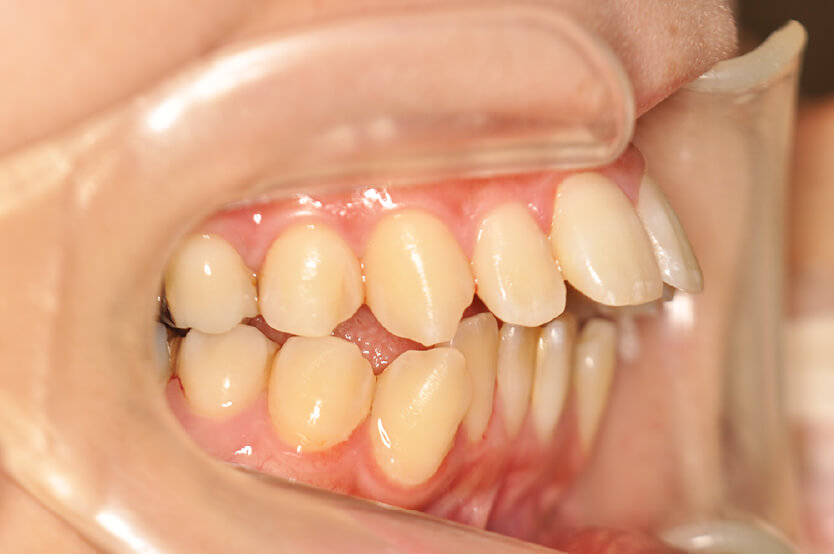

初診時

症例 症例 症例 症例

年齢

25歳 性 別 女性

治療内容の詳細 初診時25歳の女性で、出っ歯で口元が出ているのを気にされ来院されました。

検査の結果、上顎前突、上下顎前歯部叢生および開咬を伴うアングルⅡ級1類不正咬合と診断しました。